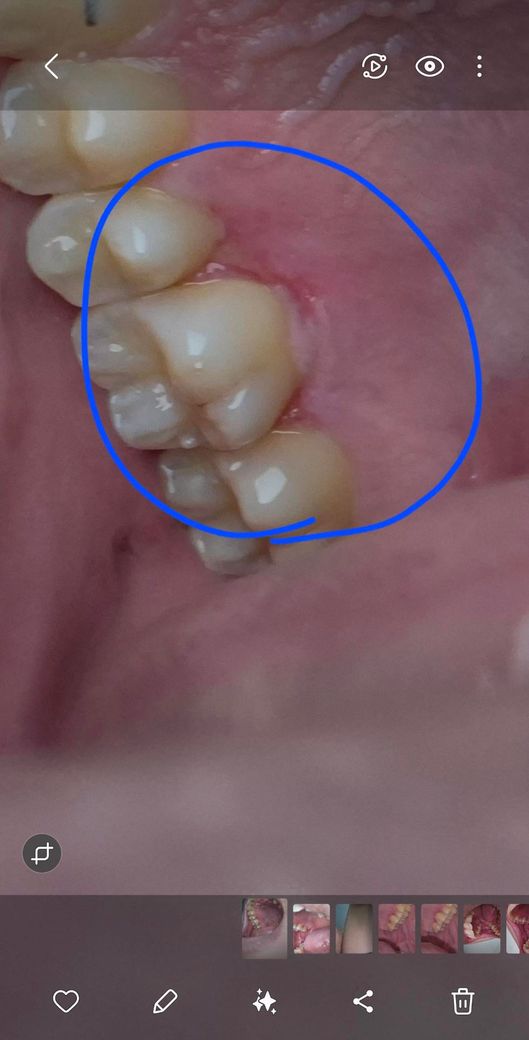

잇몸에 상처같은게있는데 건들면 아파요ㅠ

안건들면 괜찮은데 밥먹을때나 건드리면 아파요ㅠ 위험한걸까요ㅠ 파란색 동그라미 친부분이고 3~4일정도 된것같아요 궁금합니다ㅠ

사진에 보이는부분이 뜨거운거나 자극을 받아서 상처가 생긴거 같으니 당분간은 자극이 가지 않도록 해주세요.

식사나 양치중 생긴 상처로 보여지나 해당부위 염증이 자주 생기는 부위라면 치은염 또는 치주염일 가능성도 있으니 근처 치과에 가서 필요시 방사선 사진 촬영과 함께 상담받아보시는것도 좋을거 같습니다.

양치질이나 딱딱한 음식등으로 인해서 해당부위에 상처가 생긴것으로 보입니다. 이런 상처는 해당부위를 자극하지 않으면 대부분 시간이 지나면서 줄어들게 됩니다.

자세한 확인을 위해서 치과에서 진료를 받아보는 것을 권유드립니다.

잇몸 질환이거나 일시적으로 생긴 구강 내 연조직 질환일 가능성이 높아 보입니다. 보통 일시적으로 생긴 증상이거나 질환이라면 2주 이내에 자연스럽게 회복됩니다. 다만 통증이나 불편감의 정도가 계속해서 커지거나 너무 불편하다면 가까운 치과를 방문하여 검진을 한 번 받아보는 것이 좋습니다. 현재로서는 x-ray 등의 자료가 없어 말씀드리기에 한계가 있습니다.

해당 부위 잇몸에 염증이 있어 생긴 병변이거나 아니면 세균, 바이러스 감염으로 인한 병소일 것 같습니다 구강내과 가보시기 바랍니다